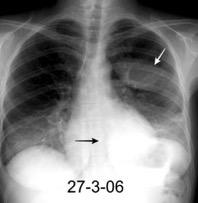

Marzo 2014: Perforación longitudinal distal secundaria a episodio de vómito (síndrome de Boerhaave). Derrame pleural izdo. que evoluciona a empiema.

Wang C-T et al. Tension hydropneumothorax in a Boerhaave syndrome patient: A case report . World J Emerg Med, 2021. Katabathina V et al. Nonvascular, nontraumatic mediastinal emergencies in adults:a comprehensive review of imaging findings. Radiographics. 2011.